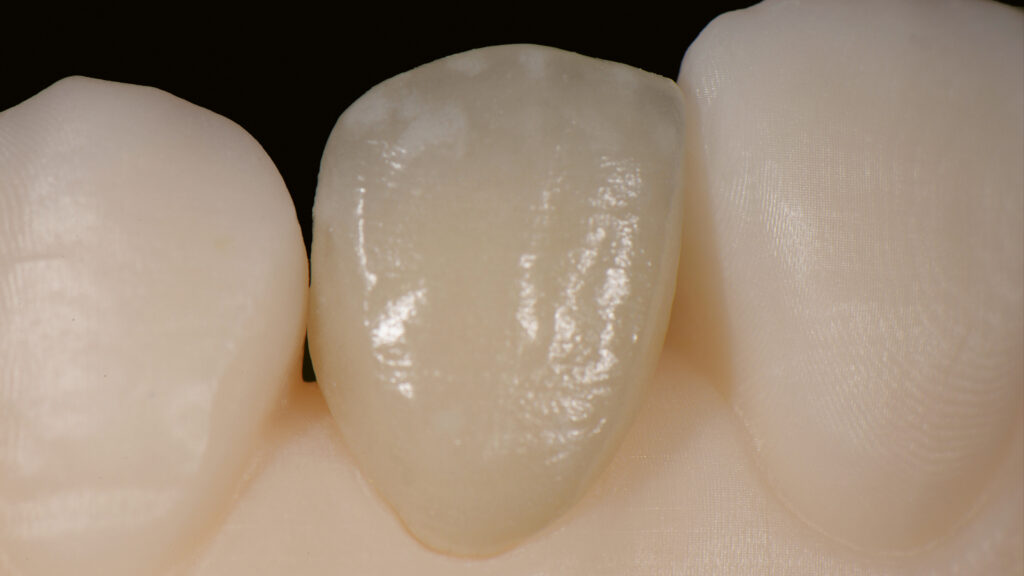

Vita Ambria (Vita Zahnfabrik, Bad Säckingen) ist ein mit Zirkonoxid verstärktes Lithiumdisilikat mit hoher Festigkeit (>500 Mpa), das in der Presstechnik verarbeitet wird. Die Keramik eignet sich besonders für die effiziente Herstellung von hochästhetischen, langlebigen Restaurationen wie Overlays und Teilkronen. Das Presskeramik-System enthält Presspellets in den Transluzenzstufen T (transluzent) und HT (hochtransluzent) (Abb. 15). Ein Vorteil ist, dass die aus Vita Ambria gepresste Restauration vollanatomisch und monolithisch bemalt und glasiert oder mit der Verblendkeramik Vita Lumex AC (Vita Zahnfabrik) fertiggestellt werden kann. Nach dem Modellieren des hauchdünnen Käppchens (Abb. 16) und dem Pressen erfolgt das Ausbetten der Keramikschale. Die minimale Reaktionsschicht kann mit geringem Druck (2 bar) abgestrahlt werden, so dass passgenaue Ergebnisse effizient erzielt werden. Da die Schale in der Farbe A1 (HT-Rohling) gepresst wurde (Abb. 17) und die Schichtstärke nur 0,2 bis 0,3 mm beträgt, wirkt sie sehr transluzent (Abb. 18). Es folgt die Verblendung mit Vita Lumex AC. Hier zeigt sich ein weiterer Vorteil für die Umsetzung dieses Falles. Denn die Verblendkeramik kann auch auf Zirkonoxidgerüsten verwendet werden. Vita Lumex AC ist eine leutzitverstärkte Glaskeramik zur Verblendung vollkeramischer Gerüste aus Zirkondioxid-, Lithiumdisilikat- und Feldspatkeramik sowie zur Herstellung von keramischen Veneers.

Individuelle Minimal-Schichtung

Vor dem Brand wird etwas „Smoky White“ auf das Käppchen gestreut, um den Helligkeitswert zu erhöhen (Abb. 19). Eine Aufnahme unter UV-Licht verdeutlicht die Fluoreszenz der gestreuten Keramikmasse (Abb. 20). Die Vorteile der Streutechnik sind keine Erfindung von uns. Vielmehr hat uns unser Kollege und Freund Oliver Brix darauf hingewiesen, wie solche Käppchen vorbehandelt werden können, um eine bessere Tiefenwirkung zu erzielen. Für den ersten Hauptbrand wird interdental/zervikal eine dünne Schicht Effekt-Chroma aufgetragen und die anatomische Form mit etwas Dentin A1 ergänzt. Nach einem Cutback (Abb. 21) des inzisalen Drittels wird eine Mischung aus Schneidemasse sowie „Light“- und „Waterdrop“-Masse (tranzluzente blau/graue Masse) im Verhältnis 1:1 als Schneideteller aufgebaut (Abb. 22). Auf Opakdentin wurde aus Platzgründen und zur besseren Sichtbarkeit der natürlichen Zahnfarbe verzichtet. Die dünne Kappe bietet genügend Transluzenz und Helligkeit, um mit einer dünnen Schicht Verblendkeramik die gewünschte Helligkeit, Sättigung und Farbe zu erzielen. Die Individualisierung der Inzisalkante erfolgt mit der wärmeren und fluoreszierenden Keramik „Saffron“, die mit Interno Liquid angemischt wird (Abb. 23). Vorteil dieser Mischung ist, dass das Liquid die Masse besser einfärbt und so die Sättigung mit bloßem Auge kontrolliert werden kann. Außerdem ist die angemischte Masse sehr plastisch und lässt sich kontrolliert auf den Inzisalteller auftragen. Zur Imitation von weißlichen Kalkflecken wird „Smoky White“ mit Interno Liquid angemischt und mit dem Pinsel in die Schneidemasse eingearbeitet (Abb. 24). Nach dem ersten Brand der minimalen Schichtung sind alle Merkmale gut sichtbar. Wie in der Natur kommen sie aus der Tiefe (Abb. 25 bis 27).

Beim zweiten Brand wird die minimale Schichtung mit „Tranzluzent Clear“ ergänzt, um eine Art Filtereffekt zu erzeugen. Dies simuliert einen 3D-Effekt (Envelope-Technik), der feine Details aus der Tiefe erscheinen lässt. Der distale Kontaktpunkt wird mit etwas Dentin aufgebaut (Abb. 28). Das Gerüst wurde aus einem HT-Rohling gepresst, um einen Chamäleoneffekt zu erzielen. Dies ist mit transparenten Massen gut möglich. Dieses Vorgehen sollte jedoch nur dann gewählt werden, wenn keine Farbveränderungen (z. B. bei verfärbten Zähnen) gewünscht sind. Grundsätzlich erspart ein detaillierter Auftrag der Keramikmassen ein aufwendiges Beschleifen der Keramikrestauration im Nachhinein (Abb. 29).

Nach dem zweiten Brand wird die Form kontrolliert, um dann auf dem ungesägten Modell die Kontaktflächen und die Ausbildung der Leisten zu überprüfen (Abb. 30 und 31). Die labialen und distalen Leisten definieren die Dimension und die Grundform des Zahnes (Abb. 32). Abschließend wird das Veneer fertiggestellt; es erfolgt ein Glanzbrand (Abb. 33). Die Feinabstimmung des Glanzgrades bei Einzelkronen ist ebenso wichtig wie alle anderen Parameter (z. B. Helligkeit, Sättigung, Farbe). Um einen matten Glanz zu erzielen, wird in diesem Fall eine kürzere Haltezeit von 30 Sekunden und eine niedrigere Endtemperatur von 745°C gewählt. Ein zu hoher Glanzgrad würde den künstlichen Zahn „verraten“. Die Oberflächenstruktur ist patientenspezifisch. In die Zahnoberfläche werden Perkymatien – feine horizontale Wachstumsrillen – eingearbeitet, die mit den Jahresringen eines Baumes vergleichbar sind. Es ist wichtig, die Oberflächentextur dem Restgebiss anzupassen. Auf der Oberfläche entstehen durch die Lichtstreuung der Mikrostruktur bestimmte Lichtreflexe (Abb. 34). Die Natur macht es vor: Durch die Beschichtung der keramischen Restauration mit Goldpulver werden die natürlichen Makro- und Mikrostrukturen deutlich sichtbar (Abb. 35). Zudem macht eine „polar_eyes“-Aufnahme (Kreuzpolfilter) die keramische Schichtung im Zahninneren sichtbar (Abb. 36). Die Aufnahme zeigt die natürliche Fluoreszenz und insbesondere die mit „Smoky White” erzielte Imitation der Kalkflecken (Abb. 37). Dem Einsetzen des Keramikveneers 22 schließt sich die implantologische Therapie regio 12 an.